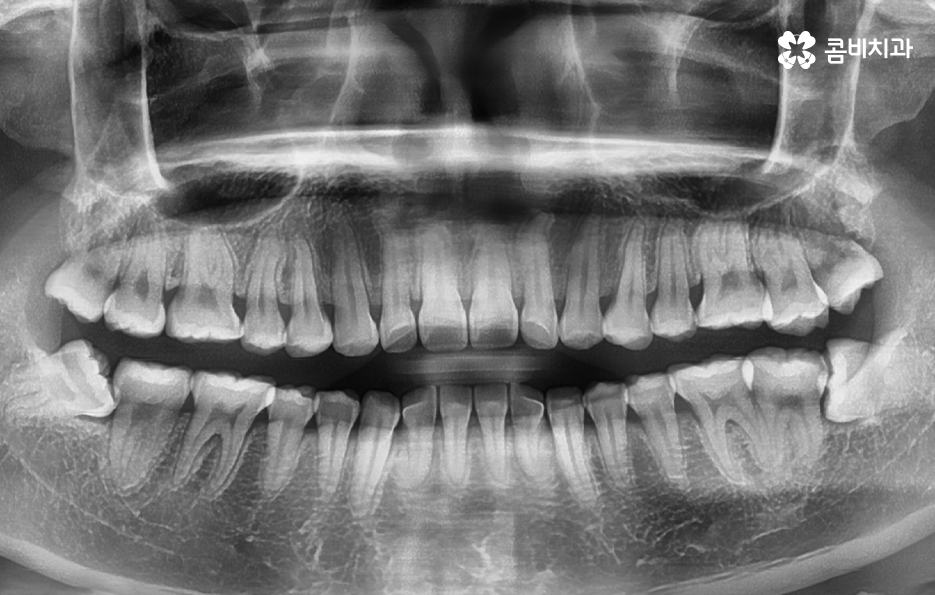

사랑니는 사람마다 다르게 생겼다고 알고는 계시겠지만 실질적으로 어떻게 생겼고 구분되는지 잘 모르시는 분들도 많을 거예요. 사랑니의 모양을 기준으로 형태를 나눠보면 똑바로 정상 맹출된 사랑니와 부분적으로 매복되어 있는 사랑니, 완전 매복되어 있는 모양으로 구분할 수 있는데요.

완전 매복되어 있는 사랑니 중에서는 어금니 쪽 방향으로 누워서 자라는 경우도 있고 어금니의 반대방향으로 누워 자라기도 하며 완전히 수평으로 매복되어 있기도 하고 수직으로 매복되어 있는 경우로도 또 다시 분류할 수 있어요.

위 환자분의 사랑니 케이스를 살펴보면 윗니의 경우 정상 맹출된 사랑니의 형태를 보이지만 아랫니의 경우에는 부분 매복되어 있고 누워서 자라고 있는 사랑니의 형태를 볼 수 있어요. 다 그런 것은 아니지만 윗니의 경우 중력에 의해 정상 맹출된 사랑니의 형태가 좀더 많다면 아랫니의 경우 매복사랑니의 형태가 많은 편이기 때문에 하악 사랑니의 발치가 좀더 어려운 경우가 있어요